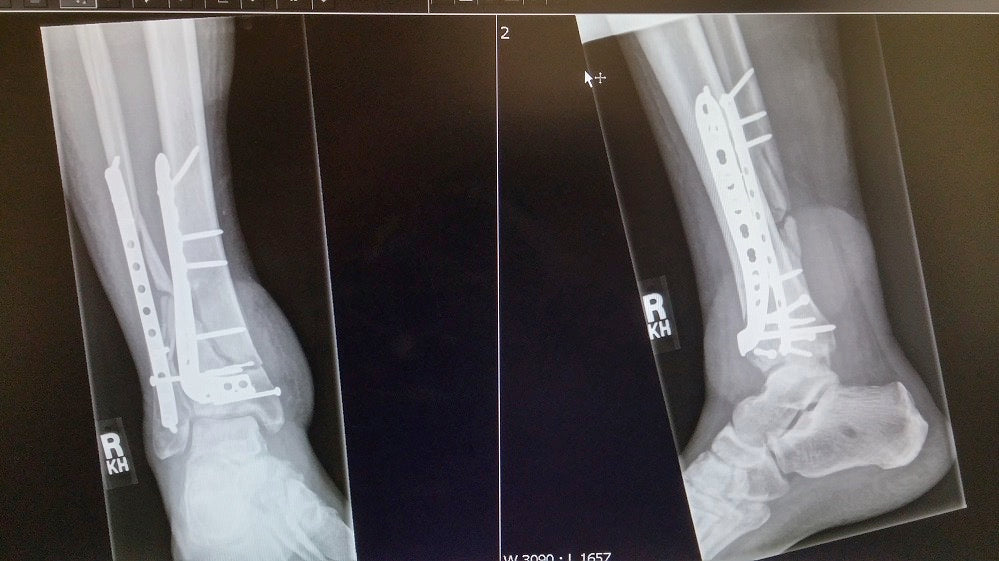

In the 3 years that followed the crash I had 13 surgeries in order to save my right leg, including two failed bone grafts and a bone transplant due to bone infection and soft tissue damage of the surrounding tissue.

Every few months after the hardware in my leg would break because the bone was not healing, I would be back on crutches and back in for another surgery. Every surgery was supposed to be the last so after attempting physiotherapy twice, I gave up on physiotherapy until I am fully healed (holding out for a few more months before I try again).